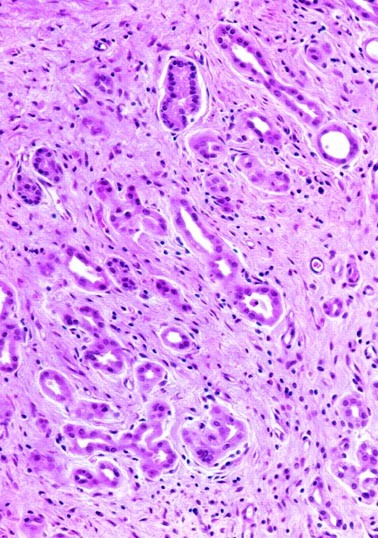

Microscopic Pathology

The microscopic features were essentially similar in all four cases. There was almost complete obliteration of the lumen by a small, poorly demarcated lesion that in two cases infiltrated the full thickness of the wall of the ureters (Fig. 2). The remaining two lesions were confined to the lamina propria. Microcystic structures containing mucin and medium-sized tubular structures predominated in three cases (Fig. 3). The microcysts were surrounded by a thickened eosinophilic basement membrane. Both the microcysts and the tubules were lined by cuboidal cells. About 10 to 15% of these cells had large nuclei and prominent nucleoli (Fig. 4). Most microcysts and medium-sized tubular structures, however, were lined by cuboidal cells with small inconspicuous nucleoli. Long, solid tubules and large, cystically dilated structures lined by flattened or cuboidal hobnail cells were seen in one case (Figs. 5 and 6). There were no papillary structures, clear cells, or mitotic figures in any of the cases. Admixed with the tubular structures and microcysts were also inflammatory cells, predominantly lymphocytes.

Several histologic features identified in the present study are worth mentioning because of the potential for confusion with clear cell adenocarcinoma or signet ring cell adenocarcinoma. Three of our cases showed focal cytologic atypia characterized by enlarged vesicular nuclei with prominent nucleoli. The term atypical nephrogenic metaplasia has been employed by Cheng et al. (11) for bladder lesions showing cytologic atypia and enlarged nucleoli but that have no clinical significance. We agree with those who believe that focal nuclear enlargement and prominent nucleoli are part of the morphologic spectrum of conventional nephrogenic metaplasia. Two lesions infiltrated the full thickness of the wall of the ureter, as described elsewhere (16). This infiltrative pattern, together with the presence of tiny microcysts containing mucin that resemble signet ring cells, may be misinterpreted as carcinoma. However, careful analysis allows identification of the tiny microcysts and exclusion of signet-ring cells. Moreover, no clear cells, papillary structures, or mitotic figures were noted in any of the four cases of nephrogenic metaplasia involving the ureter. To our knowledge, clear cell and signet ring cell adenocarcinomas have not been described in the ureter. In the bladder and urethra, these tumors are larger and show considerable cytologic atypia, mitotic figures, and foci of necrosis. Moreover, in contrast to clear cell carcinoma, all cases of ureteral nephrogenic metaplasia were p53 negative and showed a very low MIB-1 labeling index (<5%). These immunohistochemical findings are similar to those of Gilcrease et al. (9), who compared clear cell adenocarcinoma and nephrogenic metaplasia of the urethra and bladder and found that a high MIB-1 labeling index and strong p53 immunoreactivity favor clear cell carcinoma over nephrogenic metaplasia.